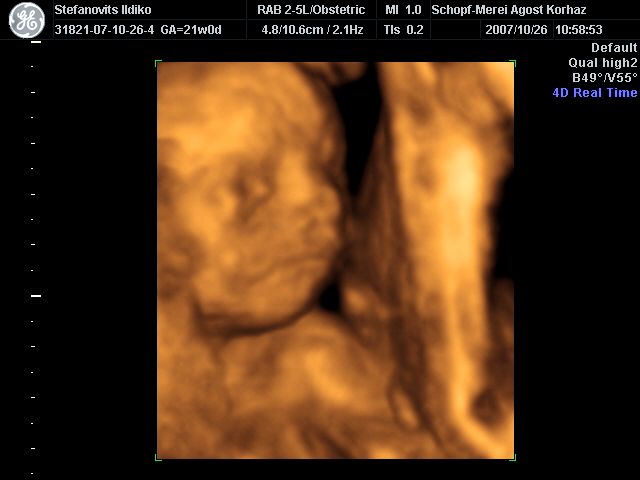

4D Ultrahang - 21+1 (07/10/26, Bp.)

4D - 13